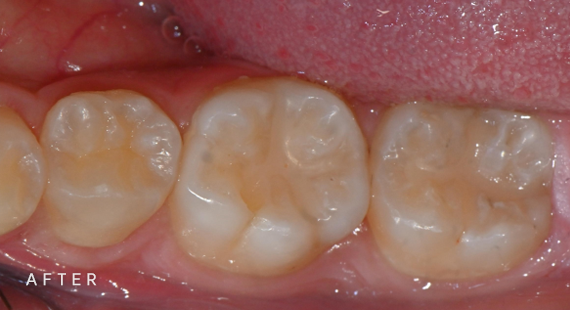

충치치료